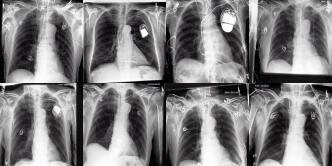

Chest X-rays We use the CheXpert dataset 10.1609/aaai.v33i01.3301590 , which contains 170k training images. This dataset contains diversity in medical devices (such as chest tubes and wires), diseases (such as pneumonia and pleural-effusion) and anatomical details. We implement Rainbow on top of frozen parameters of a finetuned Stable Diffusion v1.5 (SD1.5) by previous work kumar2025prism for chest X-ray data. We generate 2D chest X-ray images based on text prompt conditions, e.g., "Chest X-ray showing Support Devices". In addition to the finetuned SD1.5, we include RadEdit perez2024radedit , a model trained from scratch on multiple chest radiology data such as CheXpert irvin2019chexpert , MIMIC-CXR johnson2019mimic , and NIH-CXR wang2017chestxray data for image editing tasks (more details at Appendix D.3), in the result comparison. Rainbow’s graph generator module includes , , and .

Chest X-rays Figure 4b quantifies generations by Rainbow and baselines using FID and VS. Rainbow achieves a higher VS, indicating greater diversity than the finetuned SD model, while also improving image quality with a lower FID score. Both Rainbow and SD outperform the RadEdit. Figure 6 provides a qualitative comparison, images are generated using the prompt "Chest X-ray showing support devices", where Rainbow generates a more diverse set of medical devices, such as pacemakers, in all generations, while baselines do not show any devices in some images. All models achieve similar CLIP scores of . Additional results including generations, Figure 22 and numeric results, Table 4, are outlined in Appendix E.